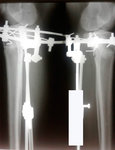

Дата операции 21.03.2018г.

Дата снятия аппаратов 06.07.2018г.

Срок лечения 105 дней.